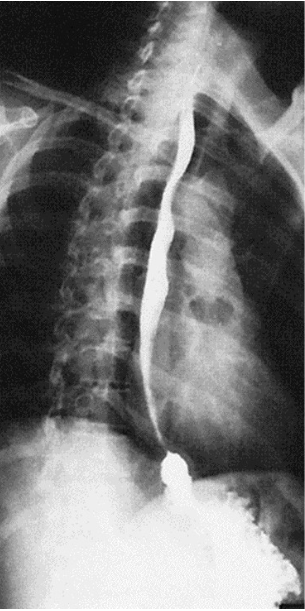

What contrast procedure was performed to produce this image?

Esophagram

1)Esophagram

2)Barium Sulfate

3)orally